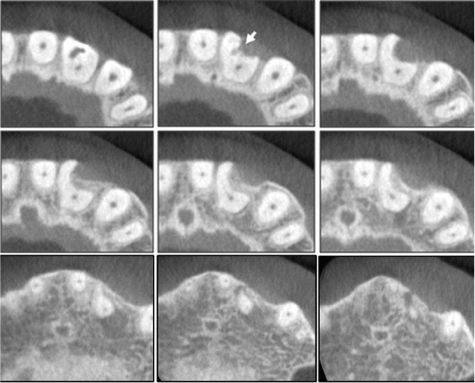

Working length was determined using an apex locator (Root ZX, Morita, Tokyo, Japan) followed by confirmation with a radiograph. The root canal was cleaned and shaped with ProTaper Universal rotary instruments (Dentsply-Maillefer, Ballaigues, Switzerland) under copious irrigation with 2.5% sodium hypochlorite. The finishing of canal preparation was performed until an F2 file reached the full working length. A plug of mineral trioxide aggregate (MTA) (ProRoot, Dentsply, Tulsa, OK, USA) was then condensed into the perforation site. After a cotton pellet was applied, the access cavity was restored with temporary sealing material (Caviton, GC, Tokyo, Japan). At the next appointment, the patient was asymptomatic, and the main root canal was dried and filled with thermoplasticized gutta-percha and sealer (AH Plus, Dentsply DeTrey, Konstanz, Germany) (

Figure 3a). The access and cervical defect were then permanently restored with a universal composite resin restorative material (Z350, 3M ESPE, St. Paul, MN, USA).

After 18 months of follow-up, there were no clinical symptoms. Recall radiographs appeared normal and showed healing of the periapical pathosis (

Figure 3b).

Figure 3(a) Radiographic view showing root fillings. White arrow indicates the MTA to repair perforation; (b) Radiographic view after 18 months showing apical healing. MTA, mineral trioxide aggregate.